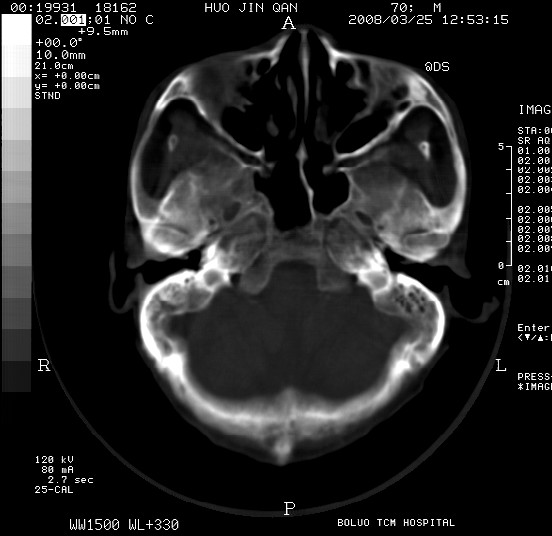

以下是引用随光逐影在2008-3-25 20:15:00的发言:[br]双侧额颞顶部亚急性(或慢性)硬膜下血肿。

以下是引用liuyue在2008-3-26 18:57:00的发言:[br]以下是引用随光逐影在2008-3-25 20:15:00的发言:[br]双侧额颞顶部亚急性(或慢性)硬膜下血肿。 [br]支持![br]可以无明显外伤病史,老年人可以在激烈摇晃或轻微头部碰创头部时,发生硬膜下出血.